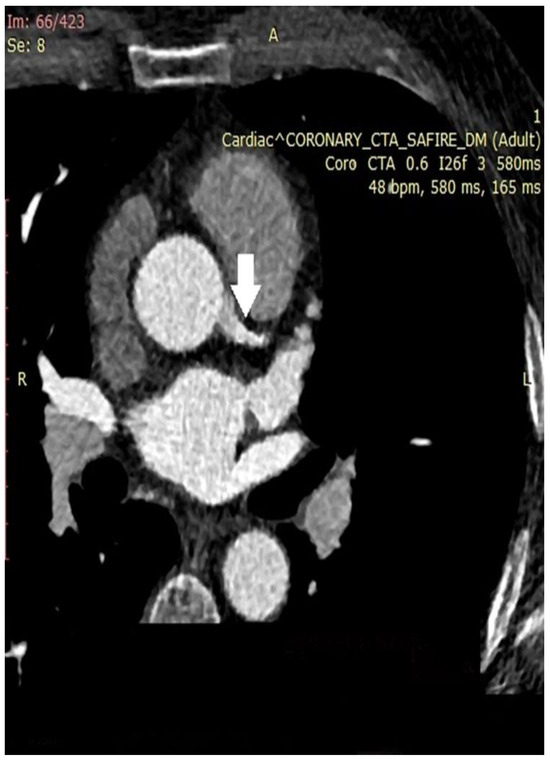

| Coronary computed tomographic angiography (CCTA) | Assess the dimensions and configuration of the arterial wall and lumen Plaque characterization Evaluating the presence, location, and characteristics of aneurysm and stenotic regions Reconstruction of intricate anatomical structures in a three-dimensional model | Noninvasive Greater specificity in cases of aneurysms and thrombosis Suitable for follow-up | Expensive Involves ionizing radiation Requires intravenous contrast media Dependent on an imaging specialist |